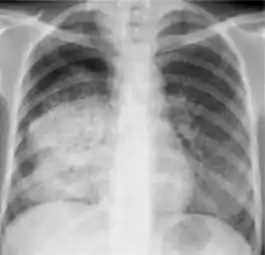

Dense homogenous opacity in right, middle and lower lobe of primary pulmonary TB.

1. Infiltrate or consolidation - Opacification of airspaces within the lung parenchyma. Consolidation or infiltrate can be dense or patchy and might have irregular, ill-defined, or hazy borders.